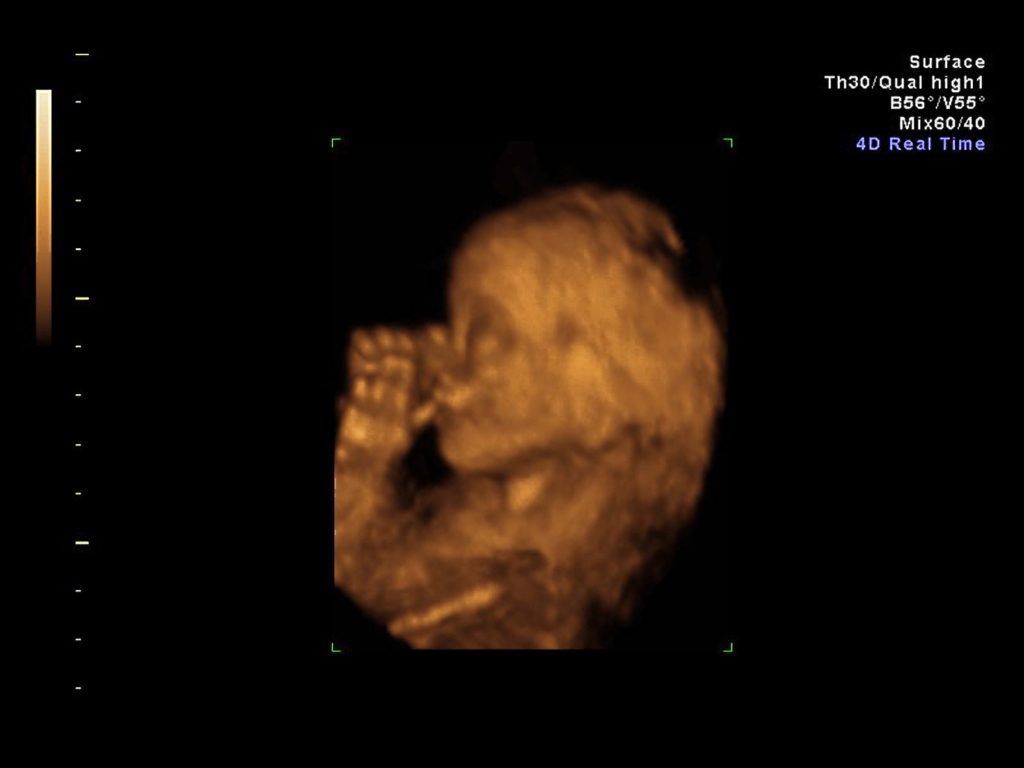

هل يبكي الأطفال داخل الرحم؟

تشعر الأم الحامل بحركة جنينها من الثلث الثاني بينما يركل ويتقلب ويميل إلى جهة دون أخرى، وقد تشعر حتى بحازوقة...